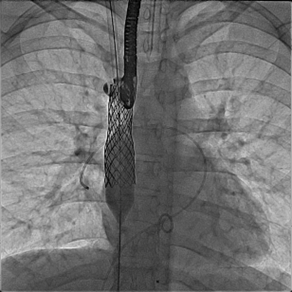

Figure 6

Fluoroscopic still image: AP view, covered stent in SVC excluding anomalous right pulmonary vein and extending to ASD part of the defect. The balloon is inflated to flare up the distal part of the stent to close the ASD. Note a catheter is kept in the anomalous pulmonary vein to continuously measure pressure and check for obstruction during and/or after the balloon is fully inflated.

AP: anteroposterior, ASD: atrial septal defect